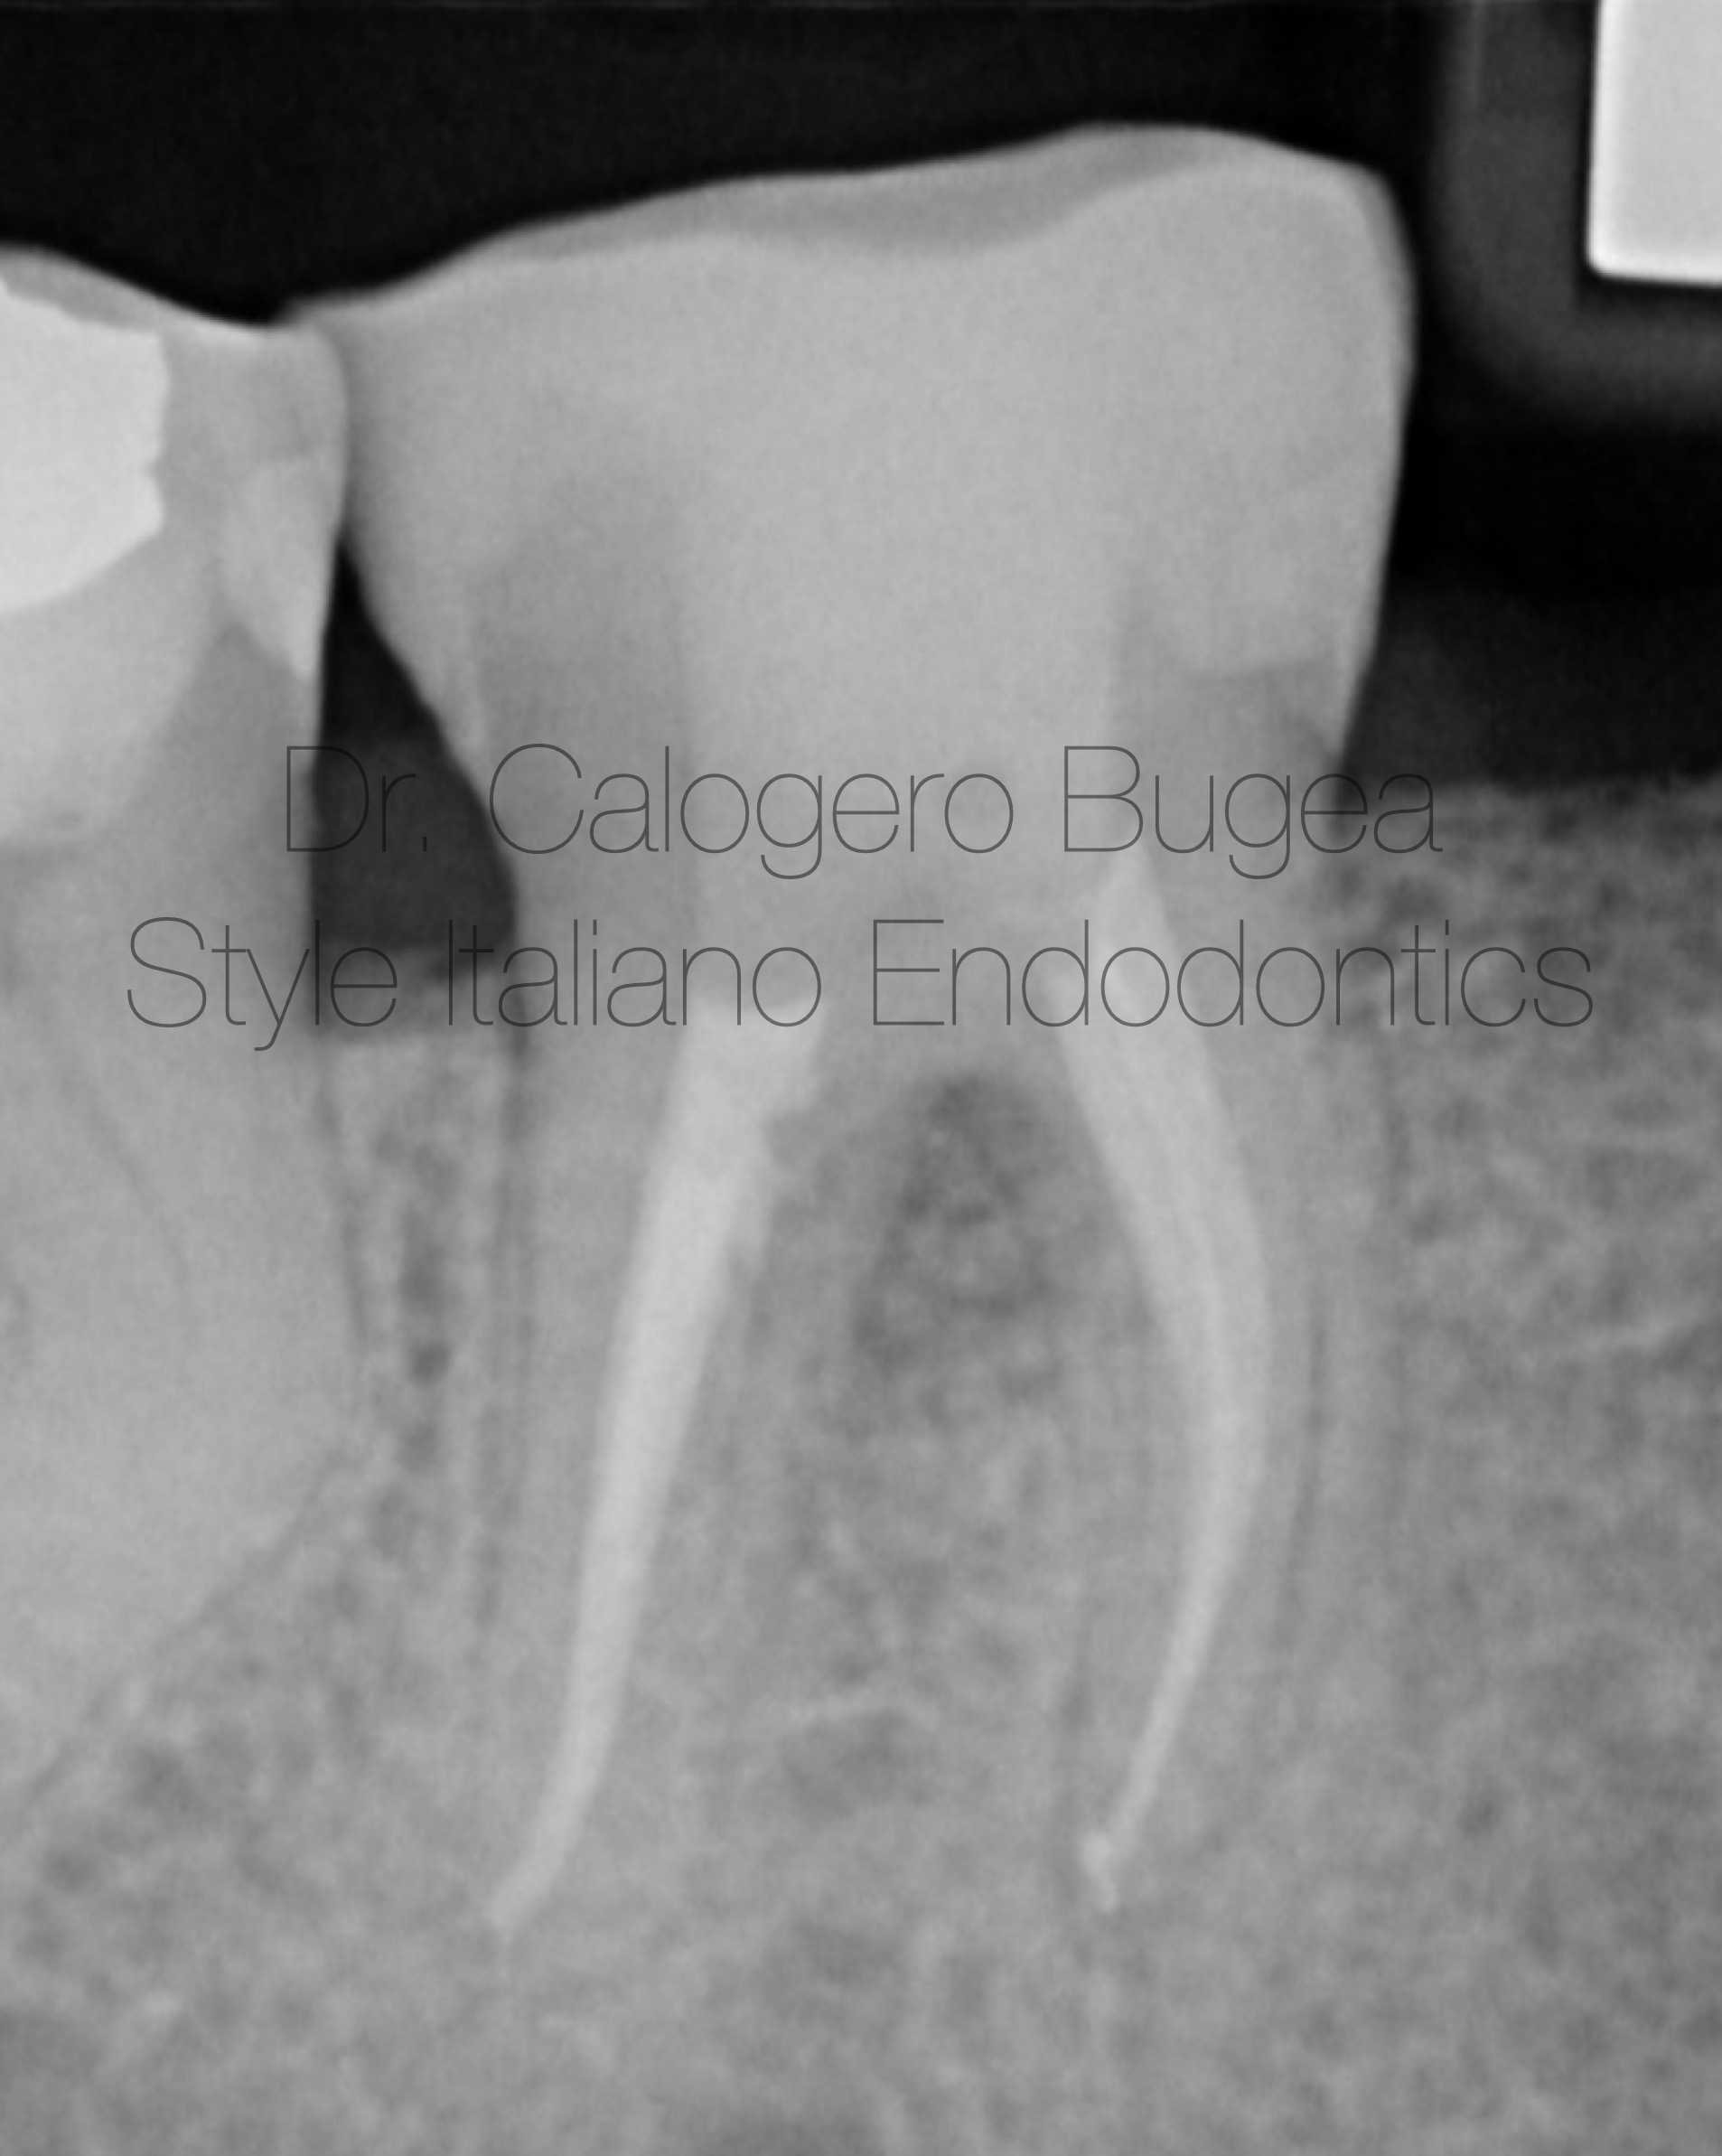

Working length Xray.